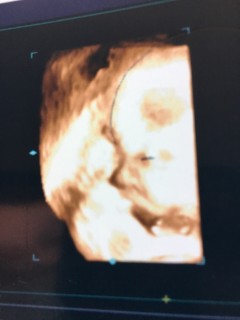

写真:32w1d:ケイトさん:こんなに開いたパー

なかなかお顔を見せてくれない息子ちゃん、今日のエコーでは手のひらを大きく開いてパーをして顔を隠していました(笑)先生もこんなに開いたパーをは珍しいね、と言ってくれました(^^)